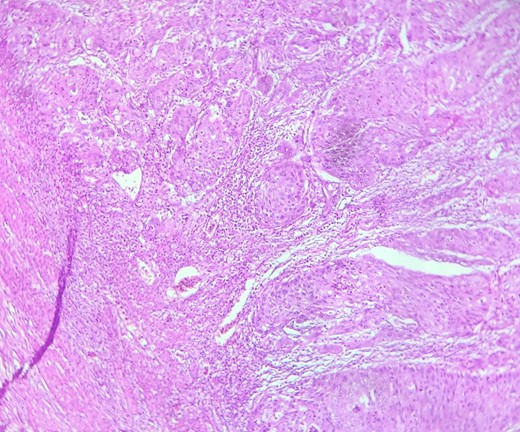

HE section showing nests and sheets of polygonal cells surrounded by fibrotic desmoplastic stroma (x100).